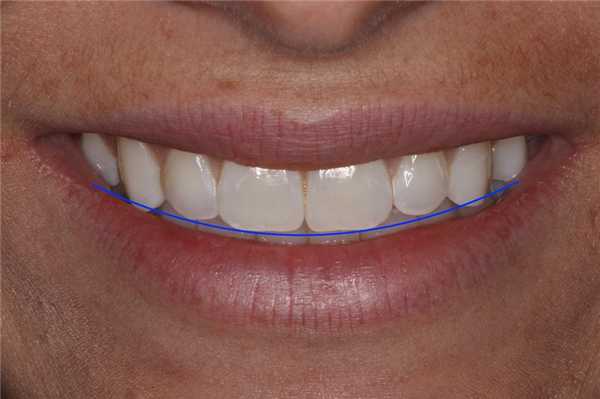

Макрофотография, или фотография крупным планом помогает оценить не только линию улыбки, но и ее соотношение с линией губ, щечным коридором, параметрами подвижности губ во время акта улыбки, и, конечно, с режущим краем верхних зубов. Важно понимать разницу между линией улыбки и линией губ. Линия улыбки является воображаемой линией, которая идет вдоль резцового края передних зубов верхней челюсти, и должна продолжаться по изгибу верхнего края нижней губы во время акта улыбки (фото 2).

Фото 2. Макрофотография: синяя линия - приблизительная линия улыбки по контуру верхних зубов (повторяет изгиб нижней губы).